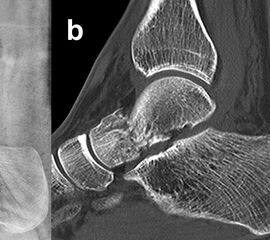

Frakturen des hinteren Taluskorpus und Proc. posterior tali

Frakturen des Proc. posterior tali und Trümmerfrakturen des hinteren Anteils des Taluskorpus (Abb. 14), die vorwiegend bei komplexen Fußverletzungen anzutreffen sind, erfordern zur Reposition und Osteosynthese aufgrund ihrer Morphologie und anatomischen Lage einen posterolateralen oder (selten) posteromedialen Zugang 4. Der Zugang liegt parallel zur Achillessehne. Im Subkutangewebe ist der N. suralis zu schonen, welcher die Faszie auf Höhe der Mittellinie durchbricht und dann nach lateral zieht. Nach Eröffnen der oberflächlichen und tiefen Faszie werden Muskelbauch und Sehne des M. flexor hallucis longus unter Schonung des medial davon verlaufenden posterioren Gefäß-Nerven-Bündels nach medial beiseite gehalten.

Der Einsatz eines Femurdistraktors, welcher zwischen Tibia und Calcaneus aufgespannt wird, kann zur Übersicht über das obere und untere Sprunggelenk sehr hilfreich sein. Die anatomische Gelenkreposition und temporäre Fixierung erfolgen unter direkter Sicht. Zur Osteosynthese kommen meist Schrauben zum Einsatz (Abb. 14). Auf eine Irritation der Gelenkflächen oder der Flexor-hallucis-longus-Sehne sollte bei Einbringen der vorzugsweise kleinkalibrigen (2,7 – 3,5 mm) Schrauben geachtet werden 4.

Zur Vollansicht und zum Lesen der Bildbeschreibung bitte das Bild anklicken.